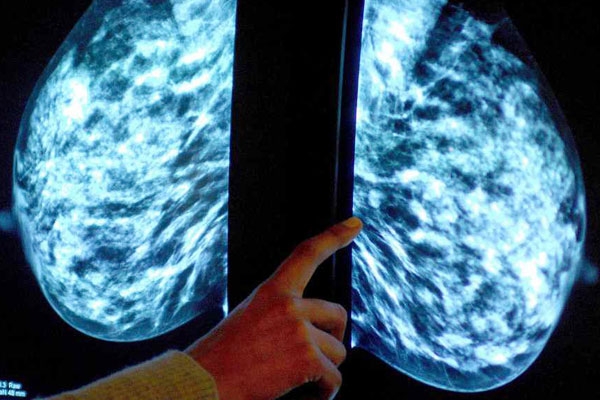

According to a worldwide study conducted by the British scientists, a shocking result appeared that most of the breast cancer victims or survivors are suffering this deadly disease because two new genetic variants associated with an increased risk of breast cancer.

The scientists from more than 130 institutions worldwide, have studied the DNA of 100,000 women, and found that genetic variants are specifically linked to the most common form of breast cancer - oestrogen receptor positive. And around 86,000 women of European, 12,000 of Asian and 2,000 of African ancestries and half of whom had breast cancer.